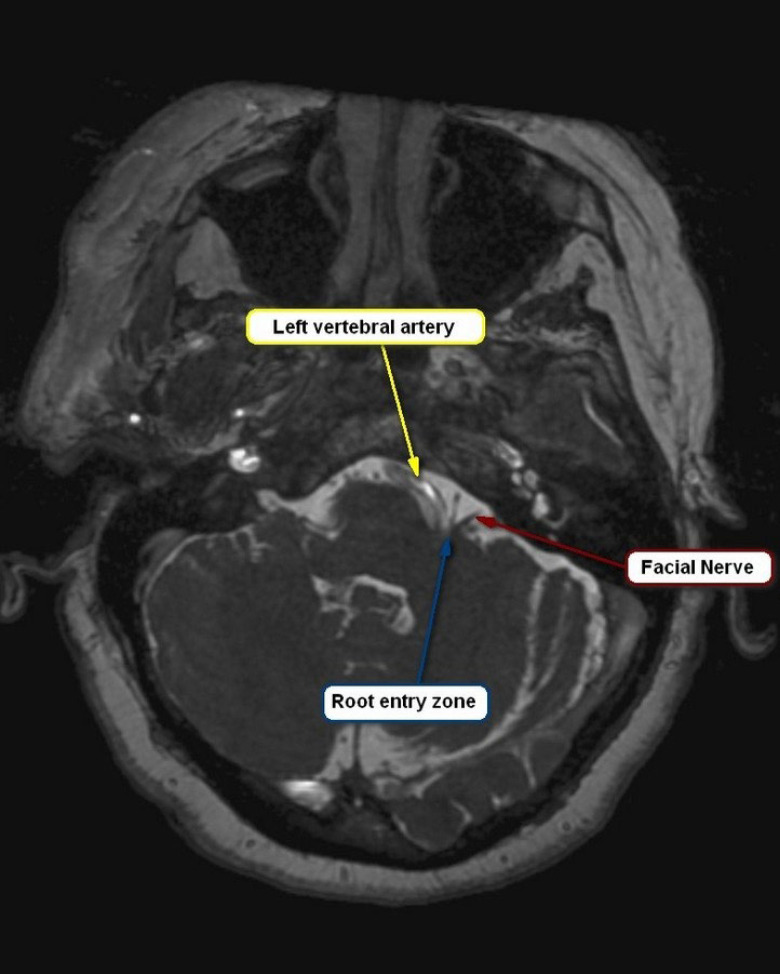

面肌痉挛(HFS)是整形外科医生需要了解的一个重要情况,因为它会显著影响患者的生活质量,并使美容和重建手术复杂化。磁共振成像(MRI)在诊断HFS、评估神经血管关系和计划治疗方面变得至关重要。MRI横断面扫描常显示面神经附着点下桥向上移位,提示HFS的神经血管受压(NVC)。对于神经外科医生来说,重要的解剖学特征包括小脑萎缩和“小后窝”,这可以通过缩小液体空间导致HFS。HFS患者的后窝通常更充血,解剖平面可能加剧椎基底动脉外侧偏曲。此外,评估乙状窦优势和其他解剖变异对手术计划至关重要,特别是在动脉高压可能影响髓质压迫的情况下。

Hemifacial spasm (HFS) is an important condition for plastic surgeons to understand, as it significantly affects patients' quality of life and can complicate aesthetic and reconstructive procedures. Magnetic resonance imaging (MRI) has become vital in diagnosing HFS, assessing neurovascular relationships, and planning treatment. Transverse MRI scans often show an upward displacement of the inferior pons at the facial nerve attachment point, signaling neurovascular compression (NVC) in HFS. Important anatomical features for neurosurgeons include cerebellar atrophy and a "small posterior fossa," which can lead to HFS by narrowing fluid spaces. The posterior fossa is often more congested in HFS patients, and anatomical flatness may exacerbate lateral deviation of the vertebrobasilar arteries. Additionally, evaluating sigmoid sinus dominance and other anatomical variations is crucial for surgical planning, particularly in cases of arterial hypertension that may affect medullary compression.